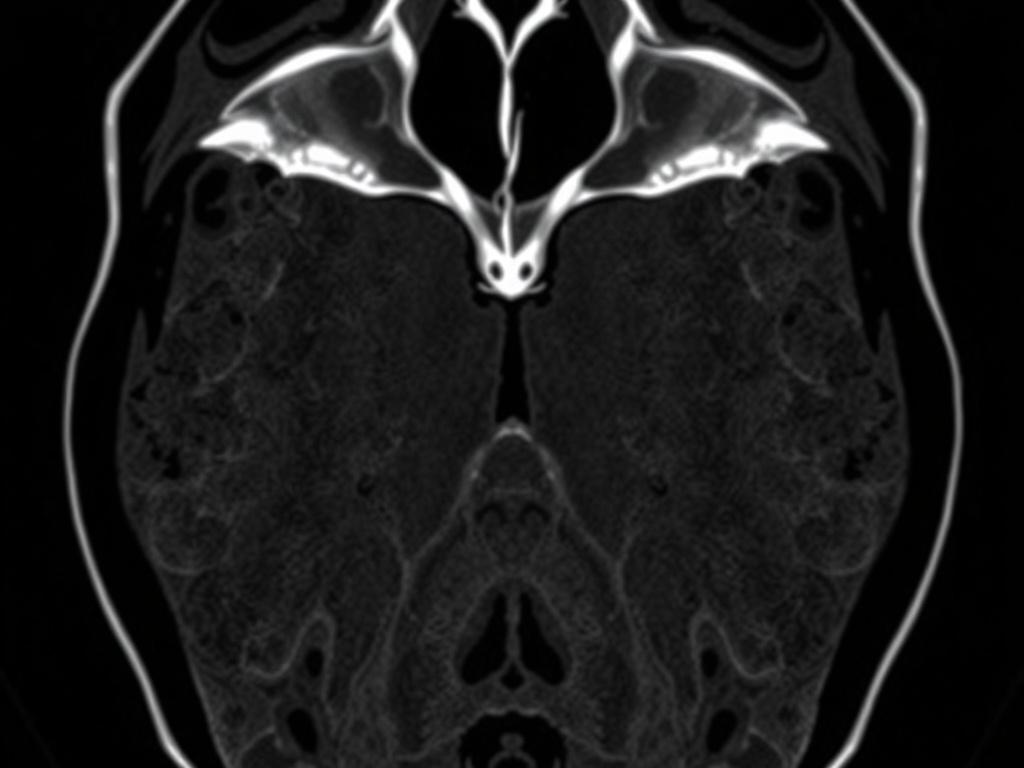

МРТ использует сильное магнитное поле и радиоволны для получения изображений органов и тканей. В отличие от КТ, где применяют рентгеновское излучение, здесь нет лучевой нагрузки, поэтому метод более безопасен для повторных исследований. Основной «герой» снимков — вода и жир в тканях: разная их концентрация и структура даёт контраст на изображениях.

Современные аппараты дают подробные срезы в нескольких плоскостях, а специальные последовательности позволяют выделять сосуды, желчные протоки или дифференцировать типы тканей. Иногда для улучшения визуализации вводят контрастное вещество на основе гадолиния, но это не всегда необходимо — многое зависит от клинической задачи.